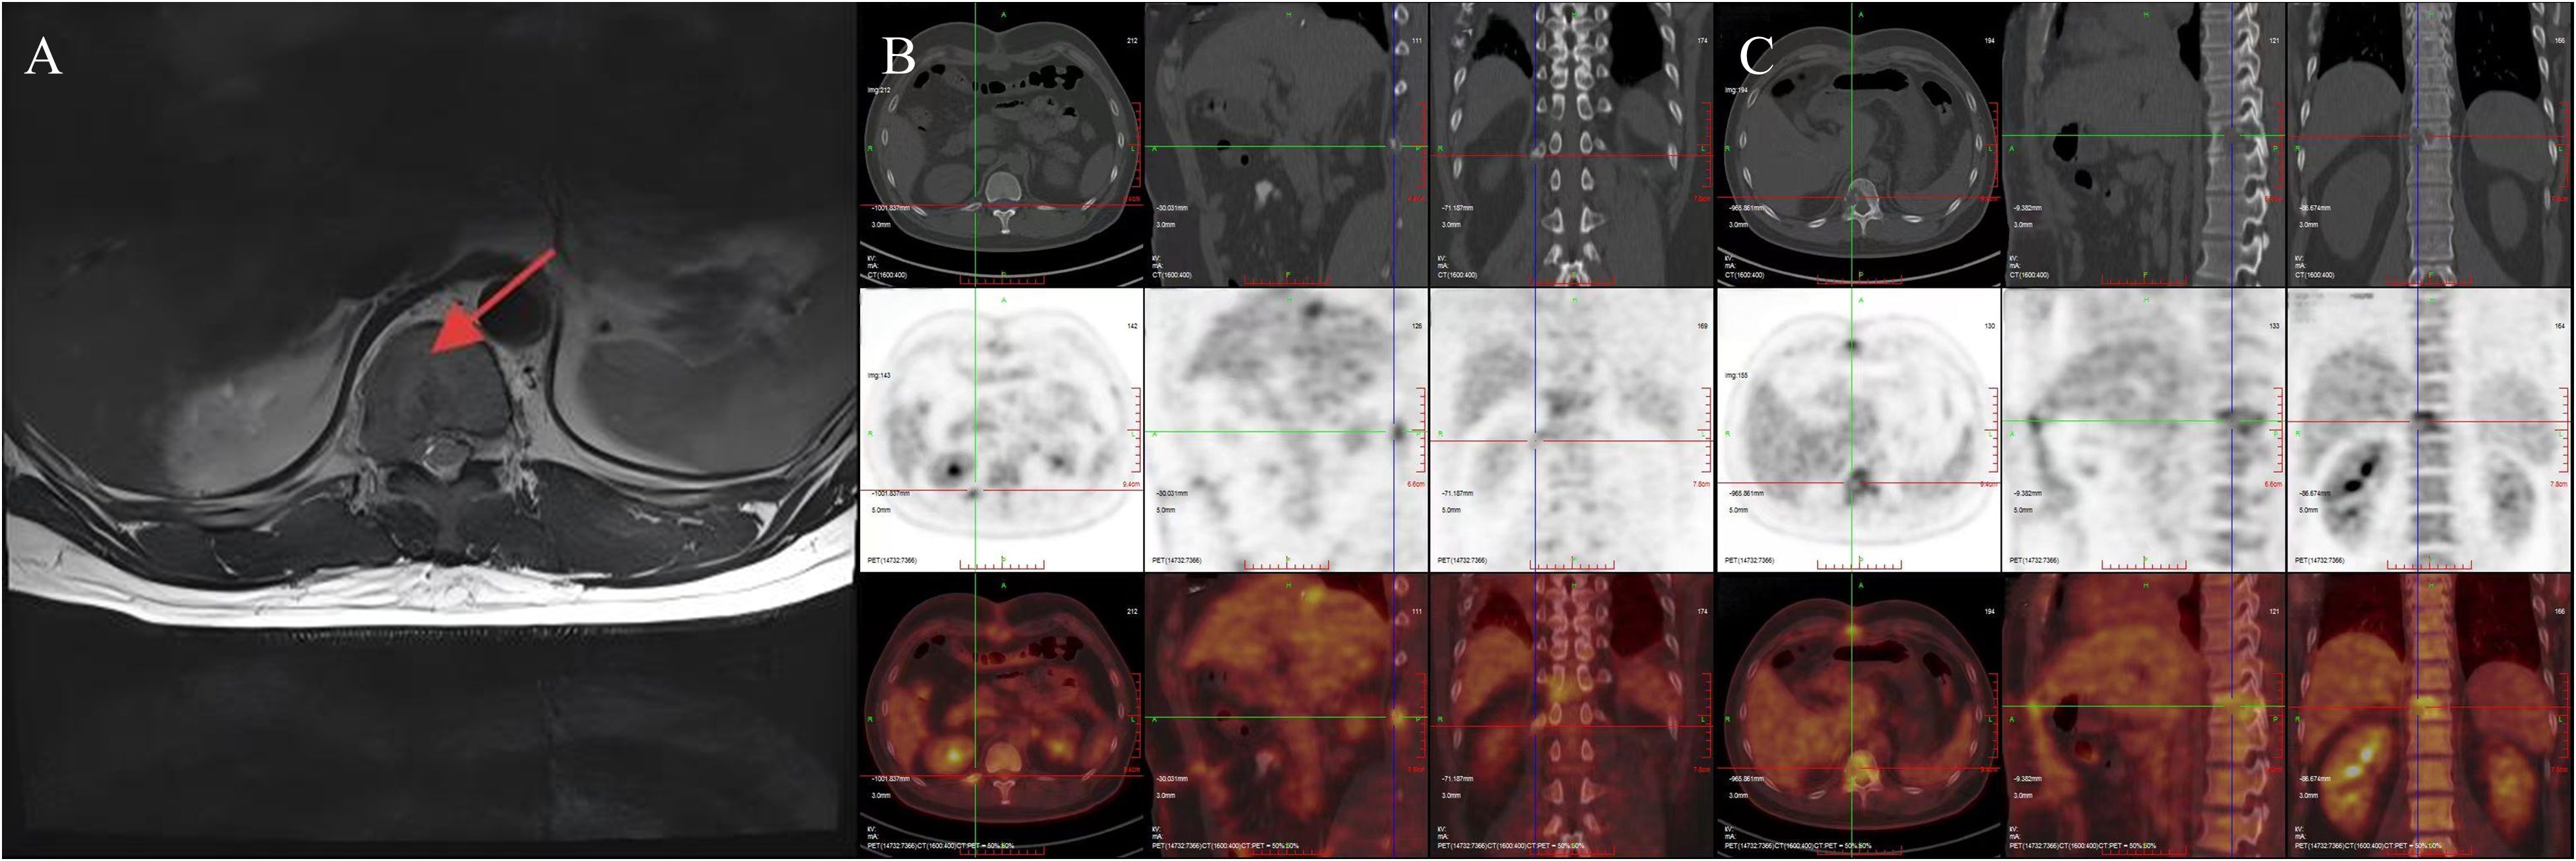

A 29-year-old male patient was admitted to our hospital in August 2024 due to “space-occupying liver lesion for 10 years and intermittent low back pain for 1 month”. The liver lesion was initially detected during a physical examination 10 years ago and was considered to be Focal nodular hyperplasia (FNH). The patient underwent regular abdominal ultrasound examinations, which revealed slow progression of the lesion. No specific diagnostic workup or treatment was administered during this period. 1 month prior to admission, the patient developed intermittent right-sided low back pain. After presentation to our hospital, abdominal contrast-enhanced computed tomography (CE-CT) demonstrated a large mass measuring approximately 8.5×11.4cm in the right hepatic lobe. Imaging features of the mass included obvious heterogeneous enhancement in the arterial phase, decreased enhancement in the venous phase, and heterogeneous hypodensity in the delayed phase, which was considered as FNH (Figure 1). The main differential diagnosis included diseases such as HCC, intrahepatic cholangiocarcinoma (ICC), hepatic hemangioma, and secondary malignant liver tumors. Laboratory tests revealed normal complete blood count (WBC: 7.02×109/L, HGB: 155g/L), normal liver function (ALT: 29U/L, AST: 2.2U/L, TBIL: 17.83μmol/L, ALB: 48.8g/L), normal kidney function(CREA: 56.2μmol/L), normal coagulation function (PT: 11.8s, INR: 0.94). The alpha-fetoprotein (AFP) level was 1.38ng/mL, and serological tests for viral hepatitis were all negative. The patient’s liver function was classified as Child-Pugh Class A. The patient denied any history of chronic diseases, viral hepatitis, or relevant familial genetic disorders. Abdominal examination showed no significant abnormalities. In addition, the patient was in good health and had not received any medication or hormonal therapy.

Figure 1

CT scan images labeled A, B, C, and D show cross-sectional views of the abdomen. The scans reveal variations in tissue density and structure, indicating different phases or conditions of an organ, likely the liver. Each image displays differences in contrast and shading, suggesting different stages or techniques in imaging.

Figure 1. Preoperative abdominal CE-CT scan revealed a space-occupying lesion in liver segments S7-8, with significant heterogeneous enhancement during the arterial phase (A), reduced enhancement during the venous phase (B) and portal phase (C), and a heterogeneous low-density shadow in the delayed phase (D). The presented cross-sections are all at the level of the T10 vertebral body.